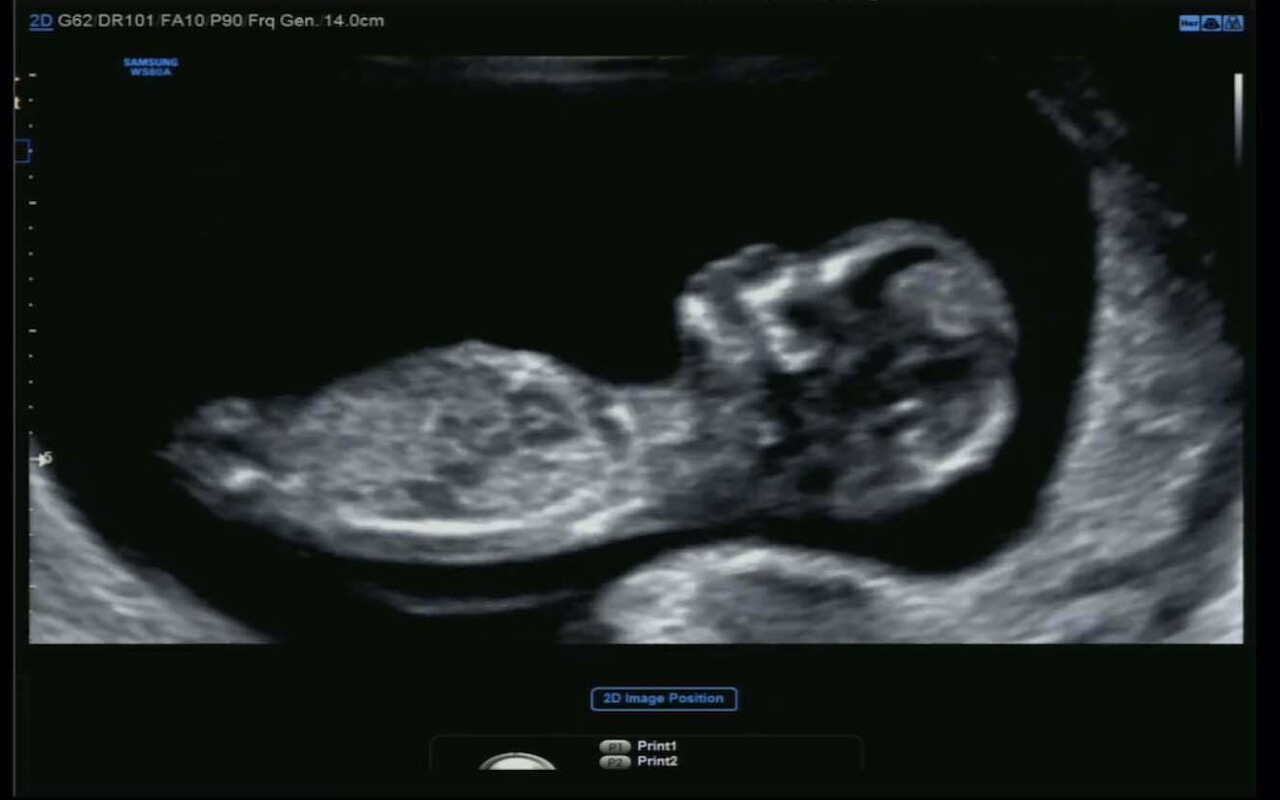

오늘(28일) 헌법재판소에서 임신 32주 이전에 태아 성별을 알려주는 것을 금지한 의료법 20조 2항에 대해 위헌 결정을 내렸습니다. 9명의 재판관 전원이 해당 조항이 헌법에 어긋난다고 판명했는데, 위헌 결정을 내린 6명(김기영 문형배 이미선 이영진 정정미 정형식)과 달리 3명(이종석 김형두 이은애)은 위헌보다는 헌법불합치로 결정하며 국회에 개선 입법 시한을 줘야 한다는 반대 의견을 냈습니다. 결국 6대3 의견으로 위헌 결정이 내려져 해당 조항은 즉시 무효가 됐습니다.

이번 위헌 결정의 이유는 시대적 변화에 따른 성평등 의식 확대. 과거 남아선호사상에 따른 여아 낙태를 막자는 취지에서 법으로 금지했지만 실효성이 없다고 본 것이죠. 또한 최근 임신중절 시기 통계 등도 결정의 근거가 됐습니다. 헌재는 "양성평등 의식이 자리잡고 유교사회 영향인 남아선호사상이 확연히 쇠퇴하고 있다"면서 "통계청 출생성비를 보면 2014년부터는 성별과 관련해 인위적 개입이 있다는 뚜렷한 징표가 보이지 않는다"고 판단했습니다. 또한 "인공임신중절의 90% 이상은 태아의 성별을 모른채 이뤄져 태아 성별과 낙태 사이에 유의미한 관련성이 있다고 보이지 않는다"고도 했죠.

그리고 부모의 알 권리를 지나치게 침해된다는 점도 작용했습니다. 헌재는 "부모가 태아의 성별을 미리 알고자 하는 것은 본능적이고 자연스러운 욕구"라며 "태아의 성별을 비롯해 모든 정보에 접근을 방해받지 않을 권리는 부모로서 당연히 누리는 권리"라고 밝혔습니다. 헌재는 "(성별 고지 금지 조항은) 태아 생명 보호라는목적 달성에 효과적이지 않고 입법수단으로서 현저하게 불합리하다"고 지적하기도 했습니다. 낙태를 금지하려면 성별을 알려주는 것을 금지할 게 아니라 낙태 관련 법개정으로 해결해야 한다는 취지죠.

태아 성 감별 금지 조항은 남녀 선별 출산, 성비 불균형을 막기 위해 1987년 제정됐습니다. 헌재는 2008년 7월 이 조항이 헌법에 맞지 않는다며 헌법 불합치 결정을 내렸고, 이에 따라 2009년 12월 임신 32주가 지나면 성별을 고지할 수 있도록 의료법이 개정돼 현재까지 시행돼왔죠. 하지만 많은 임산부들은 이를 끊임없이 알고 싶어했고, 많은 산부인과 의사들은 색깔이나 장난감 종류 등으로 눈 감고 아웅을 해야 했습니다. 32주전 부모에게 태아의 성별을 알려주면 2년 이하의 징역이나 1000만원 이하의 벌금형에 처해진다. 또 1년 범위에서 의사 자격이 정지되기도 했죠.